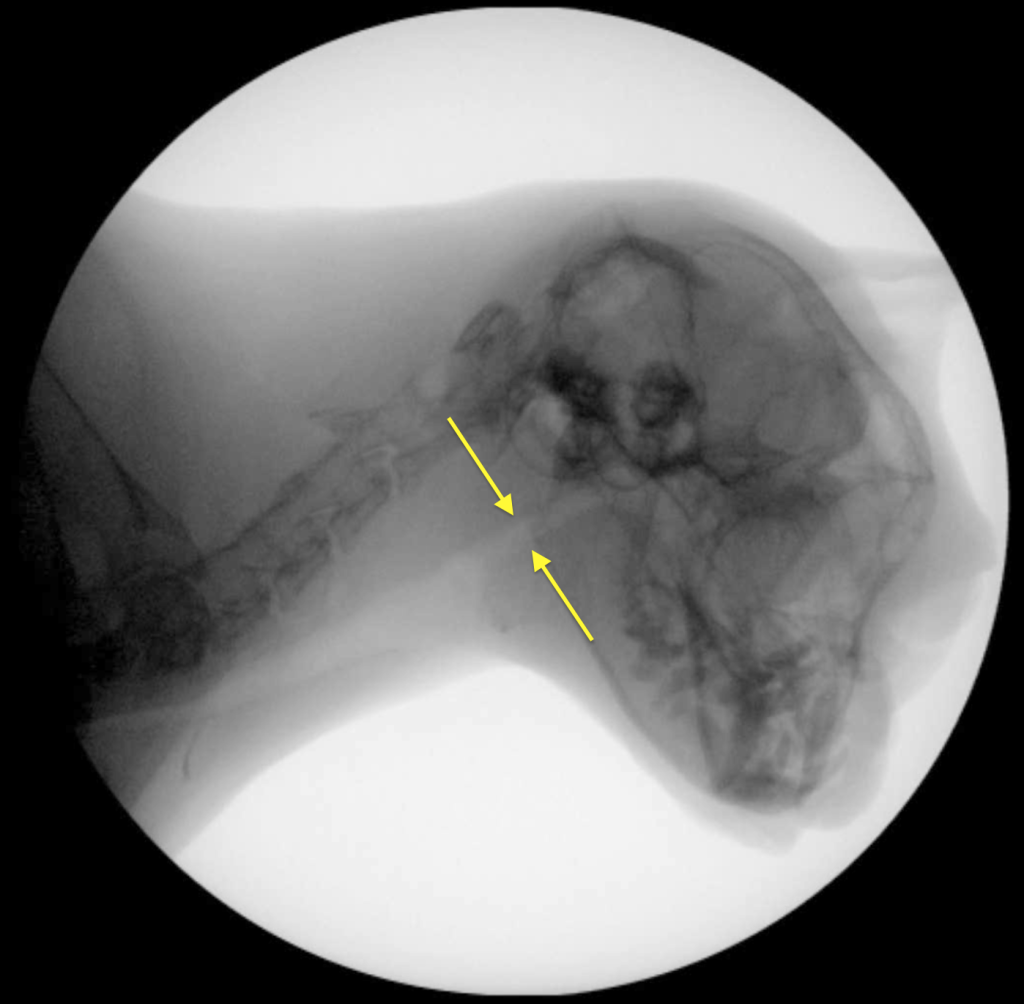

Коллапс обычно происходит во время вдоха, следовательно, это не длительное, а динамическое отклонение. Динамический назофарингеальный коллапс может быть как первичной, так и вторичной патологией5. У людей ДНФК был признан основной причиной синдрома обструктивного апноэ во сне (англ. obstructive sleep apnea syndrome; OSAS), однако в ветеринарии мелких домашних животных это состояние описывается редко, особенно у кошек5. Несмотря на сходные механизмы обструкции носоглотки у людей, собак и кошек, динамический коллапс у людей преимущественно проявляется во время сна7,8 в отличие от кошек и собак, у которых наиболее выраженные приступы одышки наблюдаются во время физической нагрузки или стресса1,2,3,5. Возможно, попытки экстраполировать методы лечения данной патологии из медицины человека являются ошибочными8.Золотым стандартом для подтверждения диагноза «динамический назофарингеальный коллапс у кошек» является рентгеноскопия акта дыхания1,2,5.

Рентгеноскопия акта дыхания проводится без седации, в естественном сидячем или стоячем положении животного.

У одного пациента коллапс проявлялся только на глубоком вдохе, у остальных трех кошек – на каждом вдохе (возможно, само исследование было стрессом для животных, что провоцировало их делать глубокие вдохи).

В результате проведенных хирургических манипуляций у всех пациентов сразу после операции нормализовалось дыхание. При проведении повторной рентгеноскопии акта дыхания ни у одного пациента не наблюдалось коллапса.